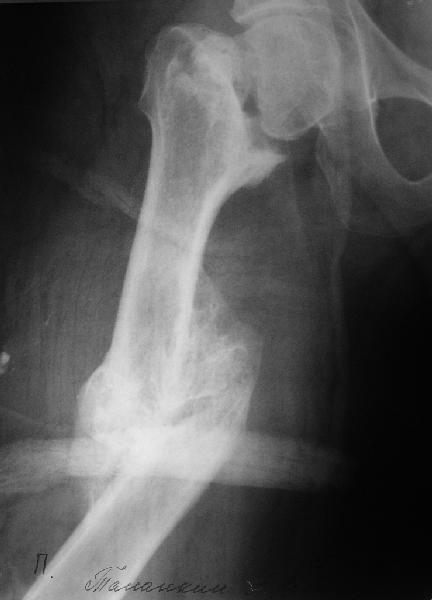

> на всякий случай сделать снимок остальной части бедра. Через 2 недели

> привезли второй снимок - тоже приложен.

Больной поступил в клинику. Дополнительные сведения: диафизарный перелом (открытый)получил 5 лет назад - падение с 5 этажа. Лечился консервативно. Через год стал ходить без трости, хромоты не было, колено гнулось ( со слов больного),В принципе был удовлетворен своим состоянием. 1,5 месяца назад упал в подъезде (в состоянии алкогольного опьянения). Отказался от 2 группы инвалидности - просто не пошел на переосвидетельствование. Живет с мамой (пенсионерка).

Вообще, судя по тому что, патология выше первичных снимков была выявлена только по просьбе консультанта, наши обсуждения носят академический характер, хотя достаточно интересные и полезные и первый эпат с коррекцией оси для данного больного будет мах достаточный.